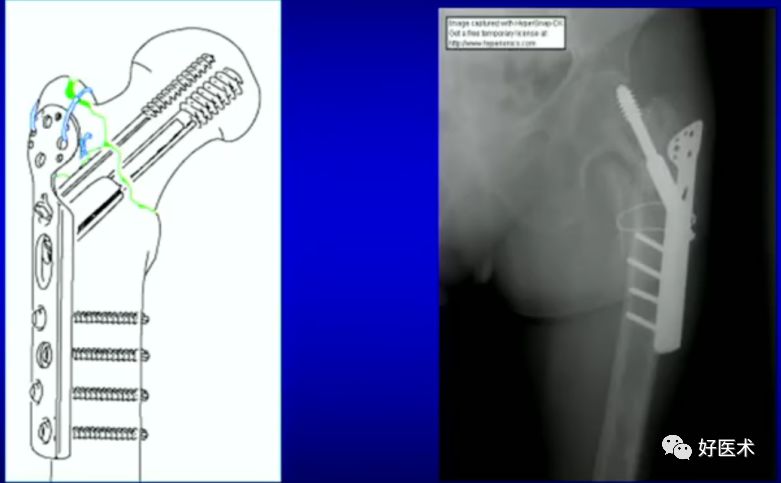

2.顶棒技术

用钉棒顶压移位骨折块来帮助复位。

病例三:女 82岁

四部分骨折,髓内钉,钢板